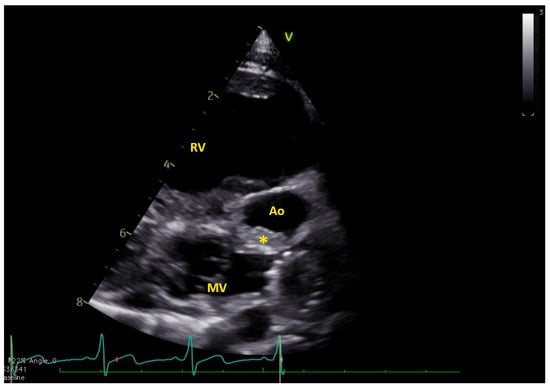

Figure 3.

(a) Long axis and (b) short axis views showing the complete thrombus resolution. Ao = native aorta; RV = right ventricle (Videos S3 and S4).